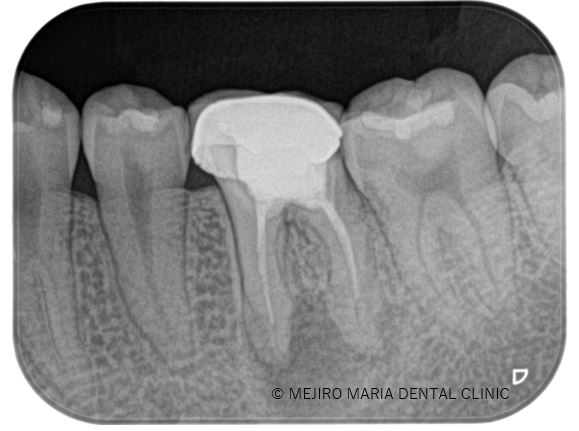

【症例】生活歯髄保存療法を用いて歯髄保存した症例−歯の神経を保存できる虫歯処置−